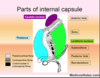

What is the boundary between the parietal and occipital lobes

It is clearly marked on the medial surface by the deep parieto-occipital sulcus

36

What are the important landmarks of the occipital cortex

Does not bear significant landmarks on lateral surface, on the medial surface the prominent calcarine sulcus indicates the locaiton of the primary visual cortex